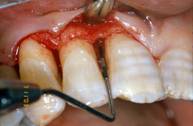

• PPD (periodontal pocket depth) [fig. 2];

•  Fig 2

Initial probing

• R: gingival recession, i.e. the position of the gingival margin with respect to the cement enamel junction (CEJ);

• CAL (clinical attachment level): i.e. the position of the attachment in relationship to the CEJ;

• IBPD (intrabony pocket depth): distance between the CEJ and the bone crest.

Periodontal pockets were measured with a manual probe marked in millimiter increments. Bleeding on probing was recorded and the presence of plaque was registred mesially, buccally, distally, and lingually. Data were obtained at baseline before treatment and at 10 days, and 6,9, and 24 months after treatment.